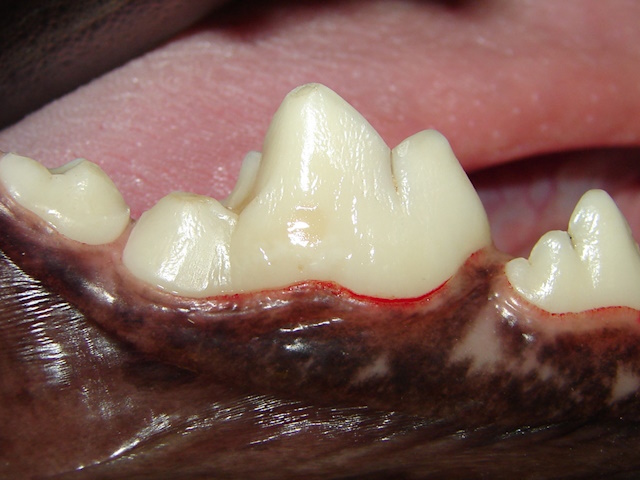

The defect is prepared and filled with composite filling material.